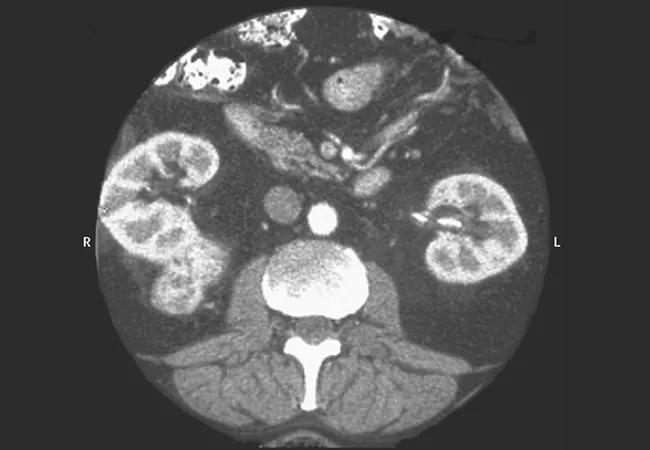

Figure reprinted with permission from Elsevier (Rini BI, Campbell SC, Escudier B. Renal cell carcinoma. Lancet. 2009;373[9669]:1119-1132).